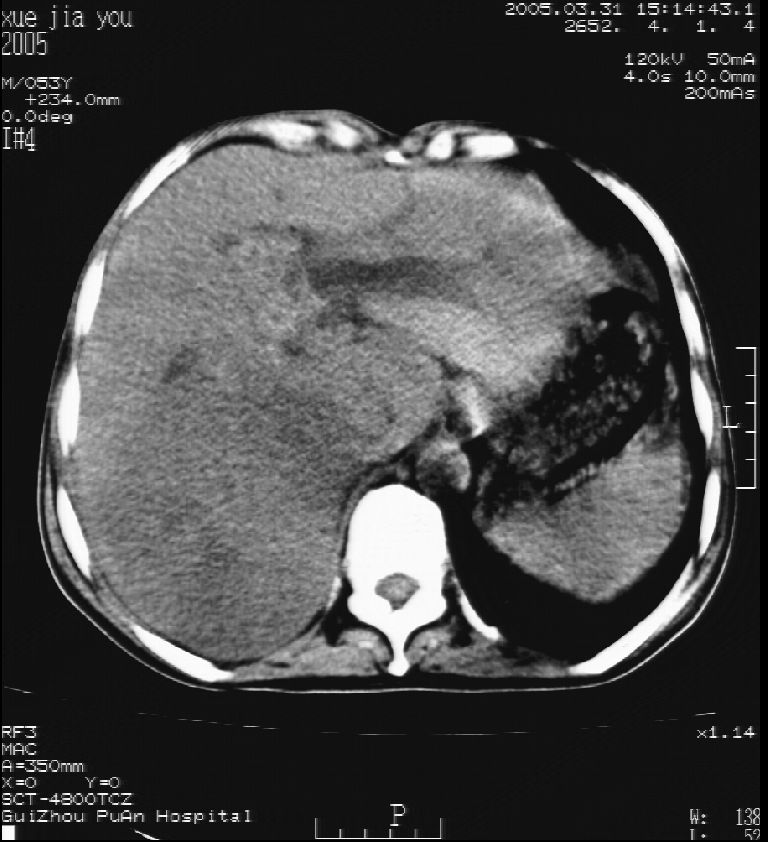

男 55岁  反复上腹痛1年,伴恶心呕吐。2005年做第一次检查后,到外院做b超检查提示肝囊肿,未做任何手术。2006年做过胆总管结石术。骨窗未见异常

这个病灶很有意思,怎么可能没有了呢?我考虑当时很可能是肝脏脓肿(b超示囊肿是有可能误诊的,因为影像表现都是低回声吗?),现在脓肿吸收了,肝脏萎缩,肝裂增宽了.别的肝叶代偿增大,不过现在左内叶的确有个占位,肝内多发结石,脾脏比以前大,不排除有肝硬化可能.建议增强扫描给于定性!!!!

肝硬化\\脾大,肝左叶肝癌可能性大,建议增强扫描.肝内胆管多发性结石.

1, 肝硬化,脾大;2,肝左叶肝癌可能性大,建议增强扫描.3,肝内胆管多发性结石.

考虑肝内胆管多发结石引起的肝内局部炎症,这样可以解释2005年肝右叶病灶的吸收和左叶新病灶.

肝硬化、脾大、肝内胆管多发结石。肝左叶低密度占位。建议增强扫描.排除肝癌